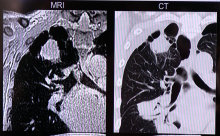

Computed Tomography (CT) | March 09, 2022

At RSNA 2021, Philips highlighted the launch of two new innovative CT systems – the multi-energy Spectral CT 7500 and the CT 5100 Incisive with embedded AI capabilities. ITN spoke with Wendy Winkle Lawless, CT Business Market Leader - North America, Philips, to learn more about these new systems.